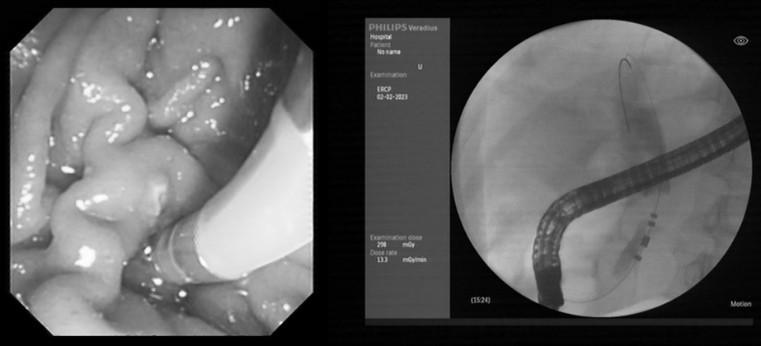

首例手术患者为一例局部晚期胰腺癌病人,失去了根治性手术的机会,同时因梗阻性黄疸且伴有糖尿病等基础疾病,一般状况较差,难以耐受化疗,常规治疗手段无法有效开展。针对该患者的病情特点,西安交通大学副校长吕毅教授、一附院肝胆外科仵正主任、胆胰内镜外科孙昊主任、胰腺外科王铮主任等经过仔细充分的术前讨论,与患者家属进行了多次医患沟通,最终决定为该患者实施内镜下脉冲电场肿瘤消融术。经过充分的术前准备,在医院麻醉手术部、介入手术室等团队的支持配合下,由肝胆外科孙昊主任医师、杨雪副主任医师、李宇主治医师、任冯刚博士等为该患者成功实施了ERCP+内镜下脉冲电场肿瘤消融术+胆道支架植入术。得益于脉冲电场能量高度密集的特点,脉冲消融过程仅用时约100秒,消融区平均温度40℃,手术过程安全可控,术后患者生命体征平稳,胆汁引流通畅,恢复顺利。2月8日,患者顺利出院。患者家属向医疗团队献上锦旗,表达真诚的谢意。患者家属眼含热泪地说:“非常感谢交大一附院的医生护士,患者刚开始状态很差,通过这次手术,患者吃饭、精神都比以前好了很多,给我们带来了希望。”

经科技查新证实,本次手术为世界首例内镜下脉冲电场肿瘤消融术治疗胰腺肿瘤。在首例患者成功救治的基础上,手术团队在春节期间又分别为一位患有壶腹部肿瘤和一位患有原发性肝癌的患者成功实施了内镜下脉冲电场肿瘤消融术。

本次手术采用了具有完全自主知识产权的国产高性能医疗器械。脉冲电场消融导管为吕毅教授团队自主研发、通过脉凝医疗实施转化的EndoPulse HPB阵列式脉冲电场消融导管,该导管头端由多支环形电极构成阵列,可以满足不同类型病变的应用需求。脉冲电场能量平台为赛诺微医疗科技与吕毅教授团队合作研发的Dophi®陡脉冲治疗仪。